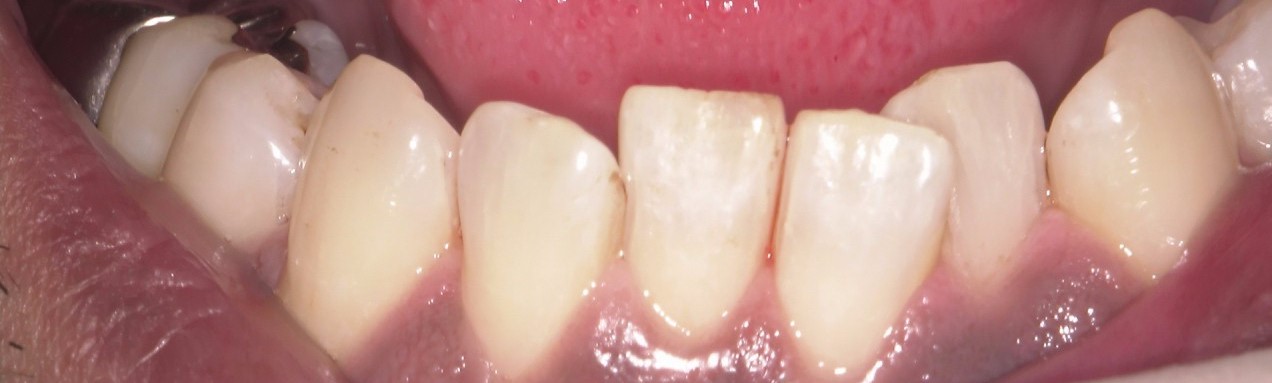

口腔内の清掃の重要性

口腔内の清掃は本当に大事です。 特に喫煙していたりコーヒーなど色が濃い食品を好む方は着色が付きやすくこべりついて不潔感がでるのはよくないと思います。 当院ではエアフローというヤニとりの専門の器具を使用して頑固な汚れもきれ […]